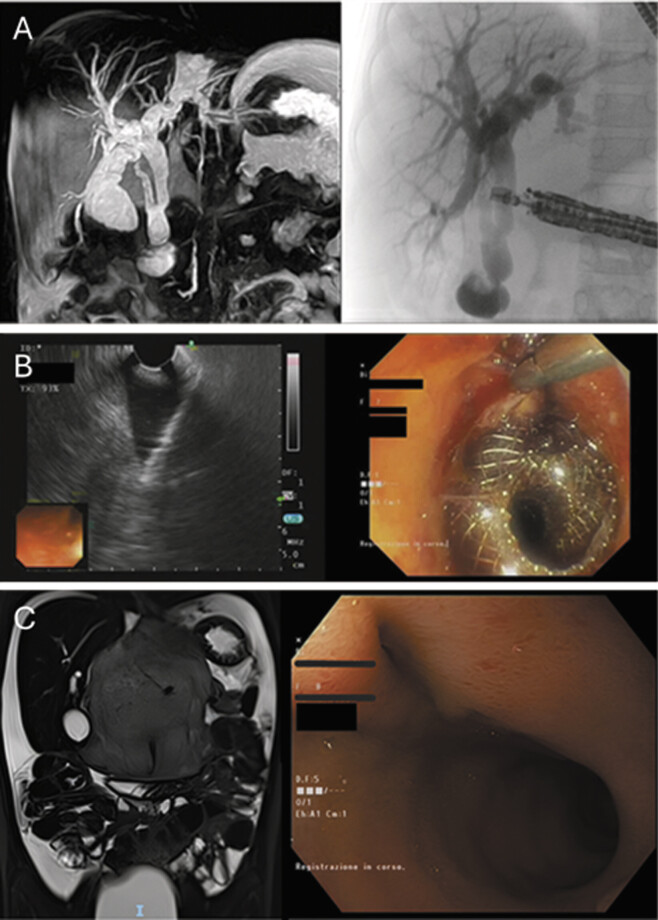

One month later, the patient presented with OJ and a progressive increase in total bilirubin levels, reaching 8.9 mg/dL. Contrast-enhanced magnetic resonance cholangiopancreatography demonstrated dilation of the left intrahepatic biliary system and gallbladder, along with complete obstruction of the distal CBD ( Fig. 2A ).

At 8 years old and weighing 20 kg, the patient underwent an endoscopic retrograde cholangiopancreatography (ERCP), which was unsuccessful due to tumor encasement of Vater’s papilla. To restore biliary drainage, an endoscopic ultrasound (EUS)-guided cholecystoduodenostomy was performed using an Olympus GF-UCT160-AL5 ultrasound endoscope, with placement of a 10 × 10 Hot AXIOS lumen-apposing metal stent (LAMS) between the dilated gallbladder and duodenum ( Fig. 2B ). The procedure lasted approximately 3 hours, although the LAMS placement itself took only 20 minutes, most of the time was spent trying to overcome CBD stricture. The main challenge in LAMS positioning was identifying an adequate acoustic window, as the duodenum, already narrow due to the patient’s small size, was significantly deformed by the tumor and the gallbladder insufficiently distended. To reduce the risk of incomplete flange deployment, the gallbladder was punctured with a fine-needle aspiration (FNA) needle and distended under EUS guidance using saline and contrast. This allowed precise LAMS placement under both EUS and fluoroscopic control. Due to the narrow duodenum, the distal flange could not be deployed under direct endoscopic vision; instead, it was released within the endoscope’s channel and advanced into the duodenum using the introducer while retracting the endoscope. The endoscopic cholecystoduodenostomy resulted in bilirubin normalization and symptom resolution. Postoperative imaging confirmed normal contrast medium passage through the biliary tree ( Fig. 2C ). According to the Clavien–Dindo classification, this complication is classified as grade 3b.

At the 3-month follow-up, the patient was in good general condition with normal bilirubin levels. Endoscopic and radiological assessments revealed a stable tumor residue and the spontaneous dislodgment of the LAMS device, alongside a stabilized cholecystoduodenostomy ( Fig. 2 ).